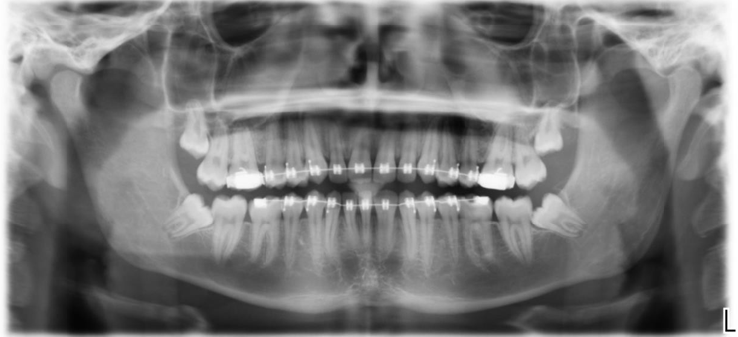

Treatment of Fused Teeth: A Case Report Study

Aljazi Hussain Aldweesh. 22(5): 56-63.